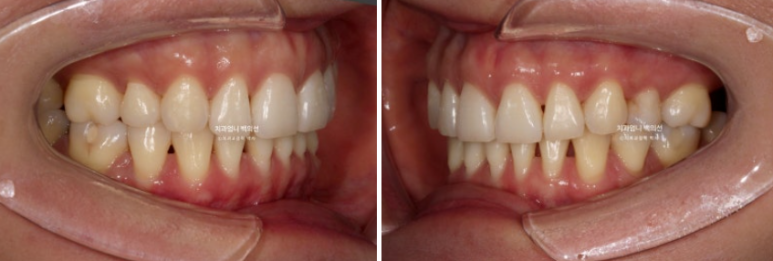

이제 앞니 중심선은 코와 인중과 정확히 맞습니다.

2급이었던 양측 어금니 교합관계는 비로소 1급이 되었습니다.

23.08~25.06

소량의 치간삭제로 기존의 블랙트라이앵글 사이즈를 줄였습니다.

옥니였던 위 앞니 각도의 개선이 뚜렷하며 뒤로 밀려있던 아래턱이 다시 나오면서 안모가 좋아졌습니다.

옥니였던 위 앞니가 역교정을 통해 정상으로 개선되어 다물었을 때 뒤로 밀렸던 아래턱이 이제 편하게 물립니다.

아래턱이 뒤로 밀리는 바람에 무턱처럼 보였던 부분도 개선이 되었습니다.